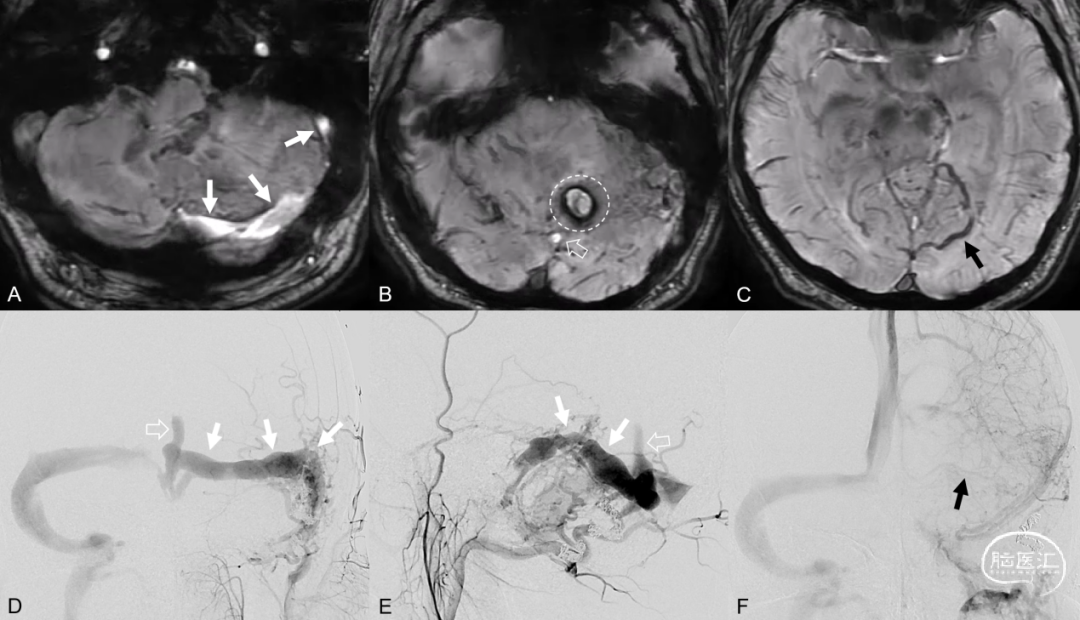

3.2.2 磁敏感加权成像(Susceptibility weighted imaging, SWI)

磁敏感加权成像 (Susceptibility weighted imaging, SWI) 可以检测脑内结构磁化率的轻微变化。动脉血中以氧合血红蛋白为主,是逆磁性物质,在SWI上表现为高信号;静脉血中以脱氧血红蛋白为主,是顺磁性物质,在SWI上表现为低信号。DAVF发生后,静脉血中脱氧血红蛋白被动脉中氧合血红蛋白置换,在SWI上可表现为静脉内高信号。利用SWI含铁血黄素低信号的特点,评估DAVF累及脑区内有无出血的发生。DAVF发生临近部位迂曲扩张静脉内是否有动脉血的引流,以此判断是引流动脉血的受累静脉,还是引流静脉血的淤滞静脉,以及推断DAVF瘘口及引流静脉所处位置。

图11. SWI显示右侧侧窦高信号-动静脉分流 (A白箭) ,提示硬脑膜动静脉瘘发生部位在右侧侧窦;直窦高信号提示硬脑膜动静脉瘘向直窦逆流 (B空箭) ,左侧小脑高信号周围低信号环 (B白环) ,提示颅内出血;瘀滞静脉低信号 (C黑箭) 。DSA造影可见右侧侧窦区硬脑膜动静脉瘘 (A、B白箭) ,向横窦及直窦逆流 (D、E空箭) ;静脉瘀滞 (F黑箭) 。